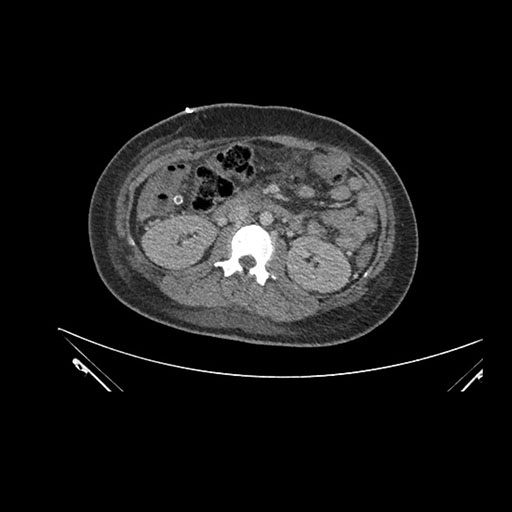

Axial Venous

Imaging analysis

Based on initial findings, which issue(s) would you be most concerned about?